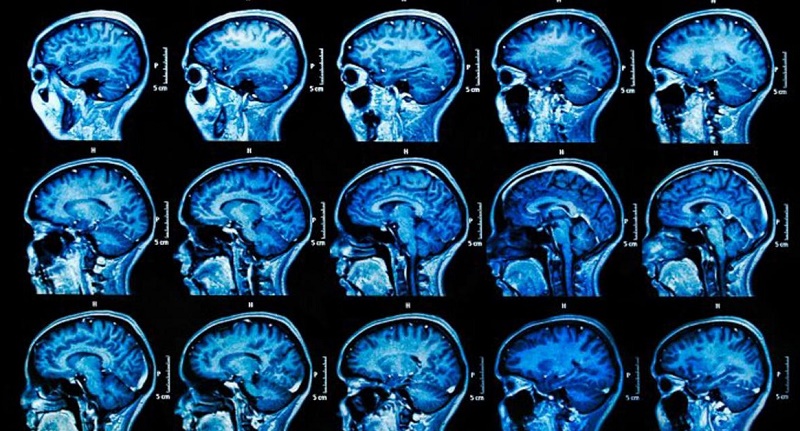

Esclerosis múltiple: la ciencia descubre el porqué de su progreso en el organismo

Un grupo de investigadores descubrió una variante genética que fomenta el avance de la esclerosos múltiple; a partir de este…